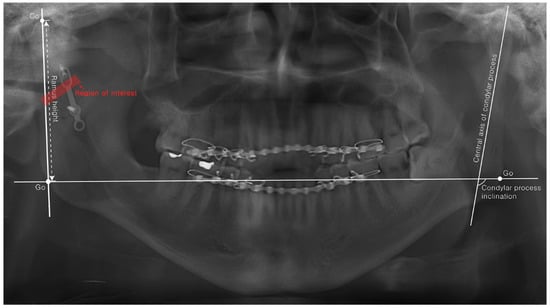

| POD 1D | POD 6M | p-Value | ||

| Differences in ramus height (mm) | Semi-rigid | 4.91 ± 3.79 | 5.50 ± 4.70 | 0.705 |

| Rigid | 3.99 ± 2.85 | 5.35 ± 3.12 | 0.124 | |

| p-Value | 0.734 | 0.786 | ||

| Differences in condylar process inclination (degree) | Semi-rigid | 6.77 ± 5.06 | 6.76 ± 8.36 | 0.723 |

| Rigid | 8.73 ± 10.61 | 12.30 ± 13.07 | 0.246 | |

| p-Value | 1.000 | 0.708 | ||

| Radio-density (Mean grayscale value of ROI) | Semi-rigid | 100.5 ± 17.4 | 102.5 ± 18.4 | 0.035 |

| Rigid | 120.7 ± 31.4 | 124.1 ± 28.7 | 0.044 | |

| p-Value | 0.041 | 0.013 | ||